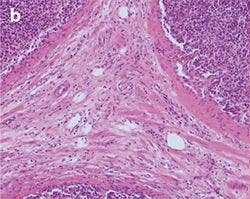

The practical effect of the color shift caused by a generic LED light source, both with and without a CC filter, is clearly visible when imaging a stained tissue section using the different light sources. Figure 5 shows a tissue section illuminated by the three different light sources mentioned before.

Figure 5: Stained Tissue Section c

Figure 5: Stained Tissue Section

Differences between halogen lamp (a) and LED illumination (b) lead to tissue stainings shifting to blue, both through the oculars and on the screen. Adding a CC filter (c) mitigates the issue, but still gives a yellowish appearance.